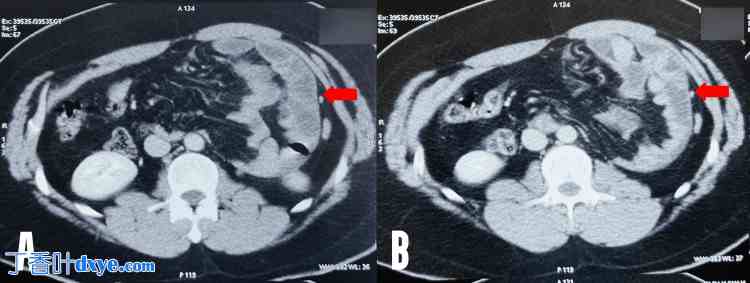

手术在全身麻醉下进行。外科医生从患者右侧进行操作。在脐下插入一个10毫米的摄像端口。在中线两侧肋缘下方5厘米处插入两个5毫米的工作端口。沿左锁骨中线(沿脐线)插入一个辅助端口,用于牵引。诊断性腹腔镜检查后,可见疝囊粘连于壁层(图 2)。

图 2. 图示疝囊粘连于壁层腹膜。